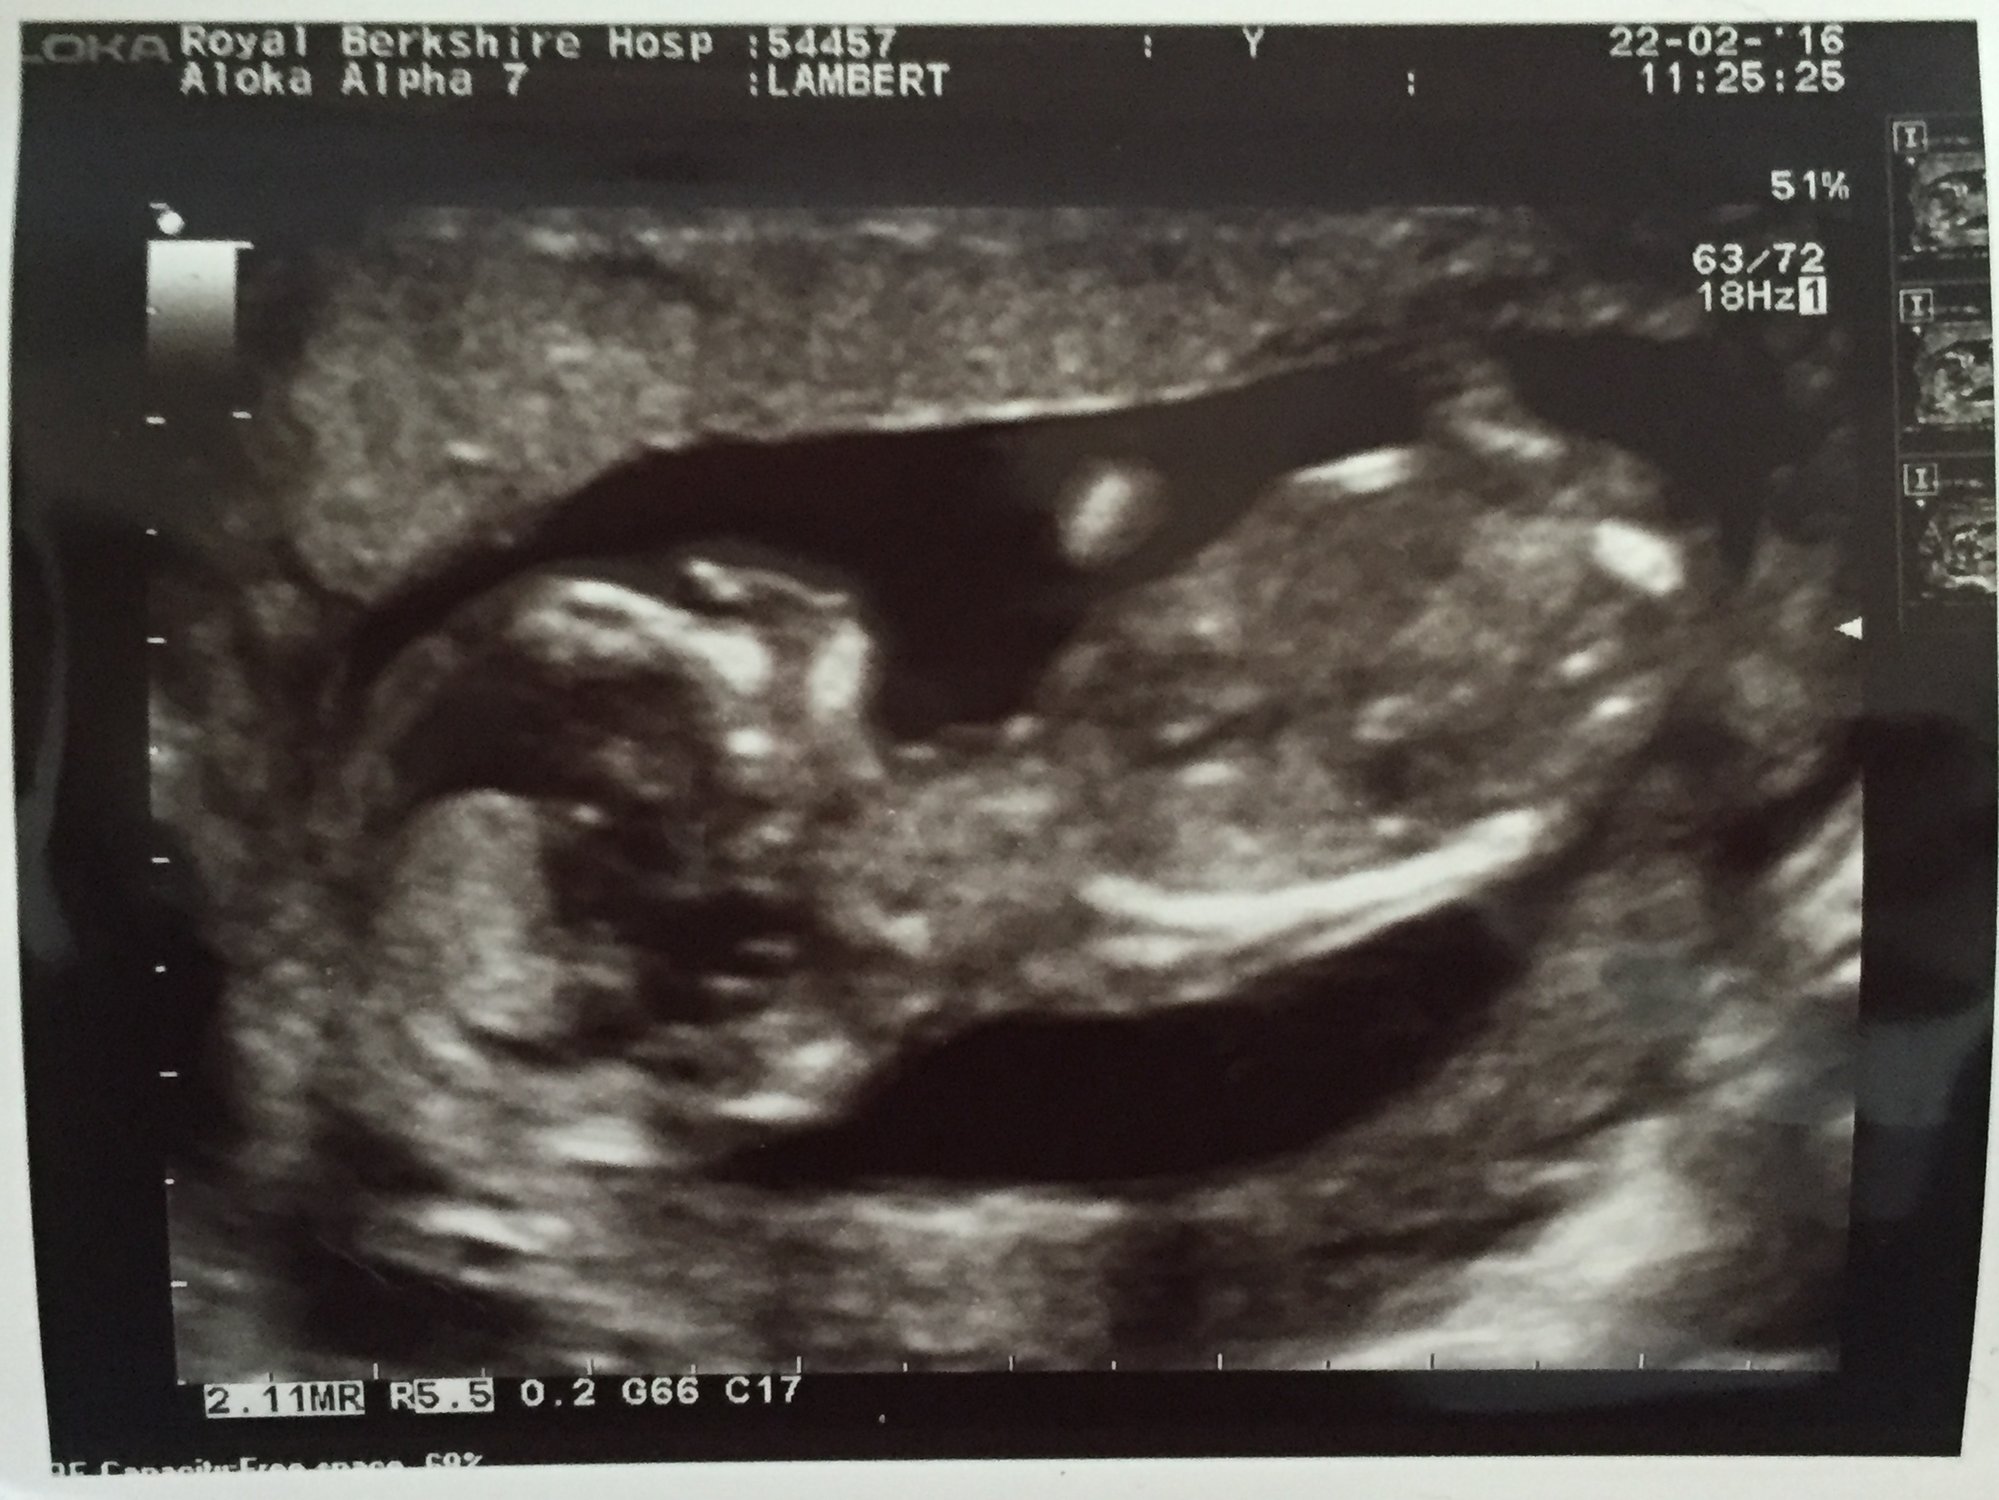

Such a brilliant start to the week... Saw our baby today and the change over the space of 6 weeks is amazing!!!

Baby Lambert

12 weeks 4 days

Heartbeat:- 155